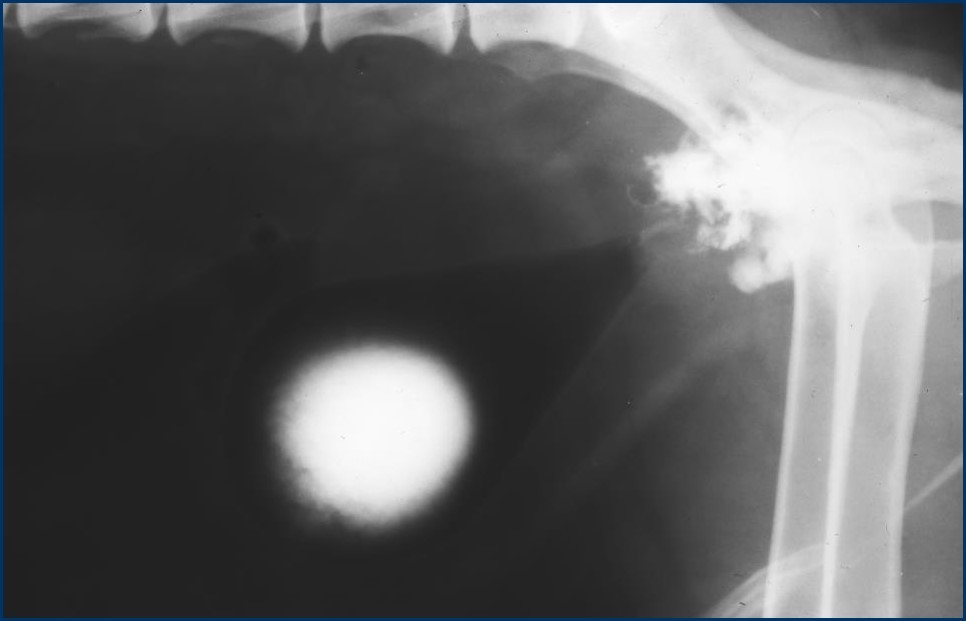

What is this?

What is the most liekly prostatic disease causing this appearance?

Pneumocysto and then contrast

Contrast has produced this appearance

What is the most likely prostatic dx causing this appearace?

Neoplasia - characteristic

NB: Cystic disease (e.g. metaplasia) – but youd never get this degree of cavity communicatin with urethra!!!